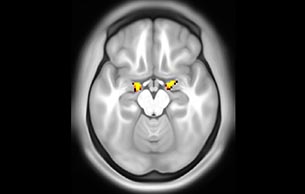

Default mode network as discovered by resting state fMRI in one participant of the ALFA cohort [7]. rs-fMRI allows us to find networks of brain regions with highly correlated activity and sustaining distinct brain functions. The default mode network (in warm color scale) is active when the brain is focused on introspective thinking and has been shown to be altered in Alzheimer’s. Interestingly, brain areas of this network are known to show abnormal levels of one of the pathological hallmarks of Alzheimer’s (b-amyloid deposition) in preclinical stages. We want to better understand the alterations of these brain networks in preclinical stages of Alzheimer's and explore their potential use as biomarkers.

Imaging was performed using Ingenia 3T CX with a 32ch dS Head coil, TR 1.6 sec, TE 35 ms, voxel size 3.1 x 3.1 x 3.1 mm, 46 slices and Multiband SENSE factor 2. Image provided by Dr. Gispert